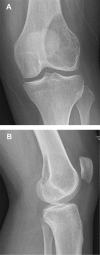

We provide an overview of imaging, histopathology, genetics, and multidisciplinary treatment of giant cell tumor of bone (GCTB), an intermediate, locally aggressive but rarely metastasizing tumor. Overexpression of receptor activator of nuclear factor κB ligand (RANKL) by mononuclear neoplastic stromal cells promotes recruitment of numerous reactive multinucleated giant cells. Conventional radiographs show a typical eccentric lytic lesion, mostly located in the meta-epiphyseal area of long bones. GCTB may also arise in the axial skeleton and very occasionally in the small bones of hands and feet. Magnetic resonance imaging is necessary to evaluate the extent of GCTB within bone and surrounding soft tissues to plan a surgical approach. Curettage with local adjuvants is the preferred treatment. Recurrence rates after curettage with phenol and polymethylmethacrylate (PMMA; 8%-27%) or cryosurgery and PMMA (0%-20%) are comparable. Resection is indicated when joint salvage is not feasible (e.g., intra-articular fracture with soft tissue component). Denosumab (RANKL inhibitor) blocks and bisphosphonates inhibit GCTB-derived osteoclast resorption. With bisphosphonates, stabilization of local and metastatic disease has been reported, although level of evidence was low. Denosumab has been studied to a larger extent and seems to be effective in facilitating intralesional surgery after therapy. Denosumab was recently registered for unresectable disease. Moderate-dose radiotherapy (40-55 Gy) is restricted to rare cases in which surgery would lead to unacceptable morbidity and RANKL inhibitors are contraindicated or unavailable.